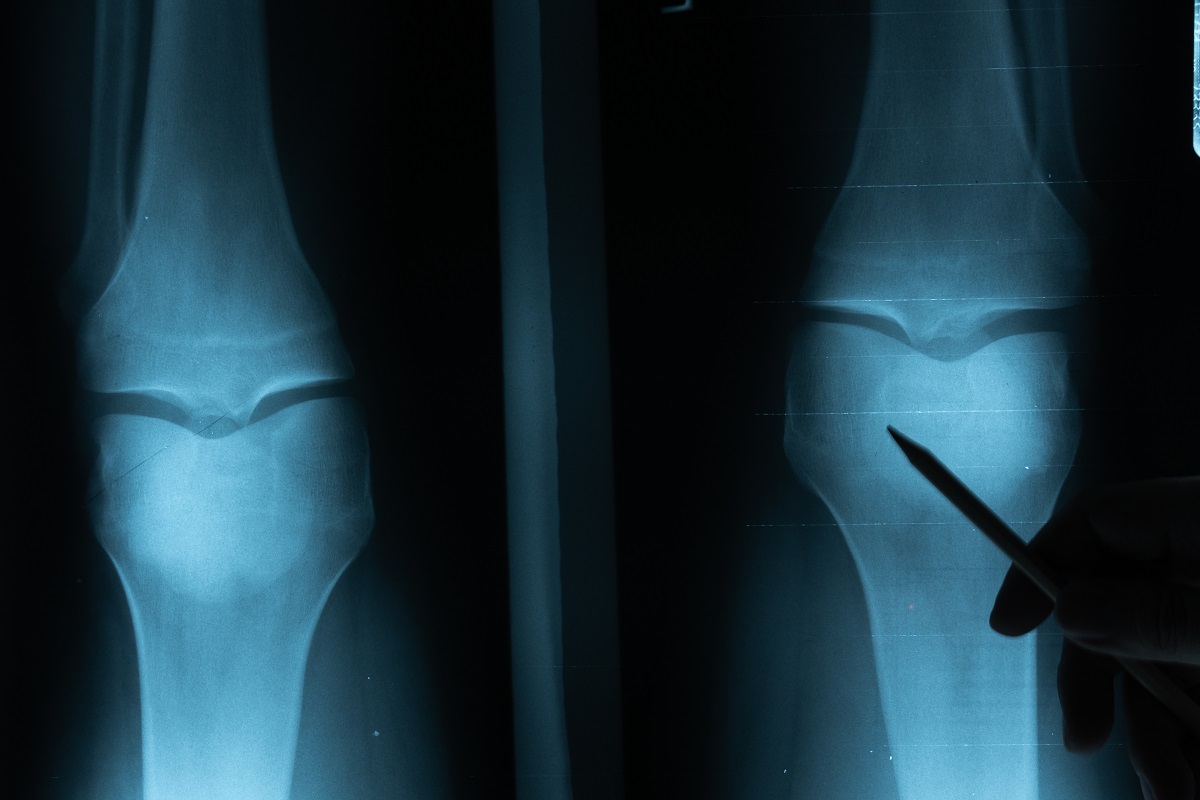

На рентгенограмме больного заметны сужение суставной щели, проявления субхондрального склероза, остеофиты (костные наросты).

• рентген;

Стоимость таких обследований может существенно различаться. Например, рентген позволяет достаточно точно подтверждать наличие артроза 2 степени, на снимках хорошо просматриваются остеофиты и места воспаления хрящевой ткани. Достоверность такой процедуры составляет более 90 %.